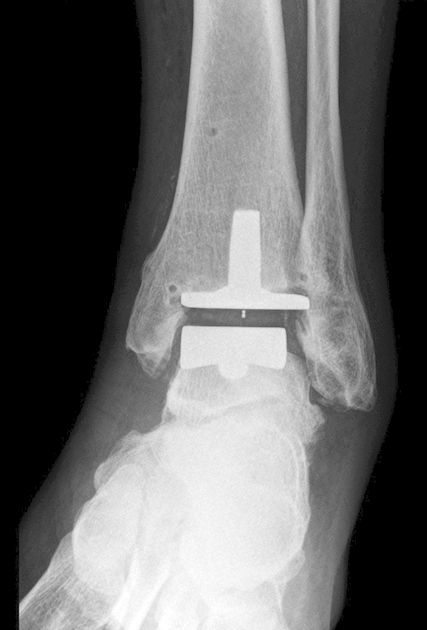

Von unserer Arbeitsgruppe wurden in den Jahren 2009–2019 92 Triple-A-Sprunggelenksprothesen implantiert. Die Triple-A-Prothese ist eine zementfreie 3-Komponenten-Prothese mit einer sphärischen Resektion des Talus, einer Stem-fixierten Tibia und einem zentral geführten mobilen Polyethylen-Inlay (Abb. 3).